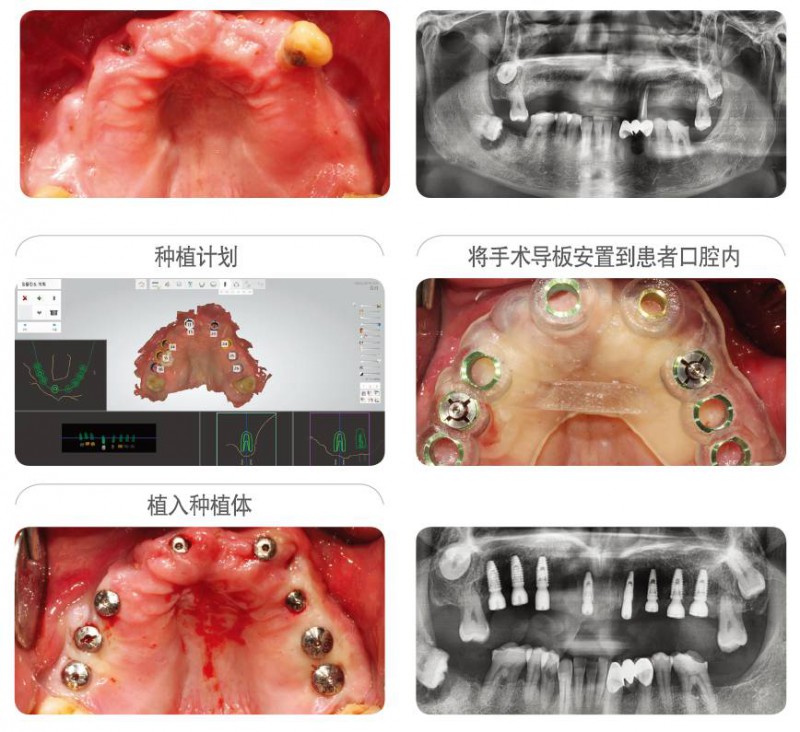

病例信息 : ST 牙科診所, 60s男性患者.

首次開展種植的牙科醫(yī)生為自己家人施術(shù)的案例.利用紐白特?cái)?shù)字化手術(shù)導(dǎo)板簡(jiǎn)單的植入8顆種植體,使得在顧問醫(yī)生的幫助下制定的治療計(jì)劃,完美的再現(xiàn)在患者口腔內(nèi)。